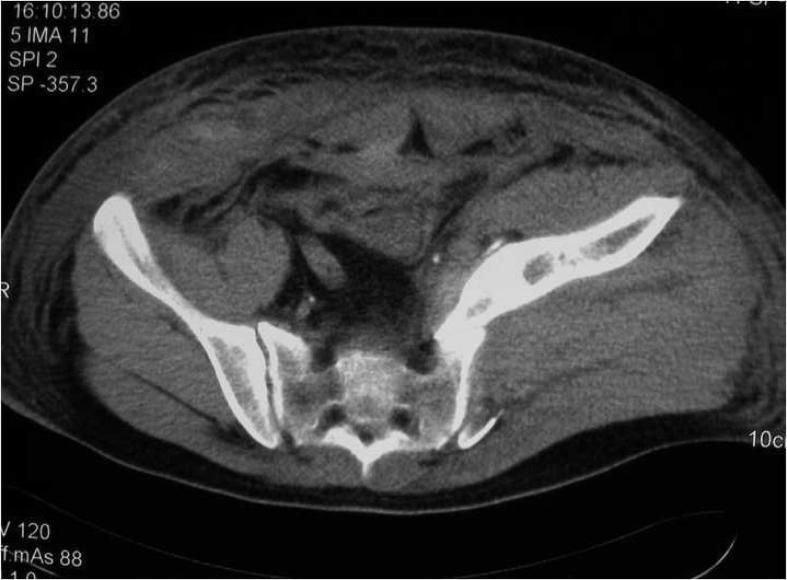

成年患者骶髂关节前脱位后隐匿性髂外静脉损伤

Occult external iliac vein injury after anterior dislocation of the sacroiliac joint in adult patient.

Anterior dislocation of the sacroiliac joint, characterized by dislocation of the ilium anterior to the sacrum, is a subtype of complete posterior pelvic ring disruption. This injury occurs mostly in children. We present an adult patient with anterior dislocation of the sacroiliac joint. It was associated with numerous complications. To the best of our knowledge, it is only the second case reported in the literature.

摘要